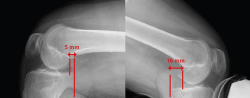

• Posterior drawer test. This is done with the patient in supine decubitus and the knee in 90° flexion. The test involves the application of pressure in a posterior direction of the proximal region of the tibia, observing posterior tibial translation in the injured knee with respect to the contralateral knee (Figure 2). A posterior displacement of the tibia of 0-5 mm is considered to correspond to a grade I lesion, 6-10 mm to a grade II lesion and >10 mm to a grade III lesion. Assessment of the degree of displacement is subjective, and thus implies important interobserver variability. If the tibial plateau remains located anterior to the medial femoral condyle, the lesion is considered to correspond to grade I, while if it is located at the same level as the femoral condyle the lesion corresponds to grade II, and if the plateau extends beyond the medial femoral condyle, the lesion corresponds to grade III (Figure 2)(10,11).

Figure 2. Initial position of the tibia reduced in the posterior drawer manoeuvre (A) compared with posterior tibial translation without reduction (B).

Posterior translation of the tibia is measured as the minimum distance between a line tangential to the posterior cortical layer of the tibia and another line tangential to the posterior margin of the femoral condyle at the most dorsal point of the Blumensaat line (Figure 5)(12,13).

Figure 5. Telos system. The red line indicates measurement of posterior translation of the tibia: the difference between the healthy right knee and the left knee is 11 mm in this case - suggestive of isolated complete posterior cruciate ligament (PCL) rupture.